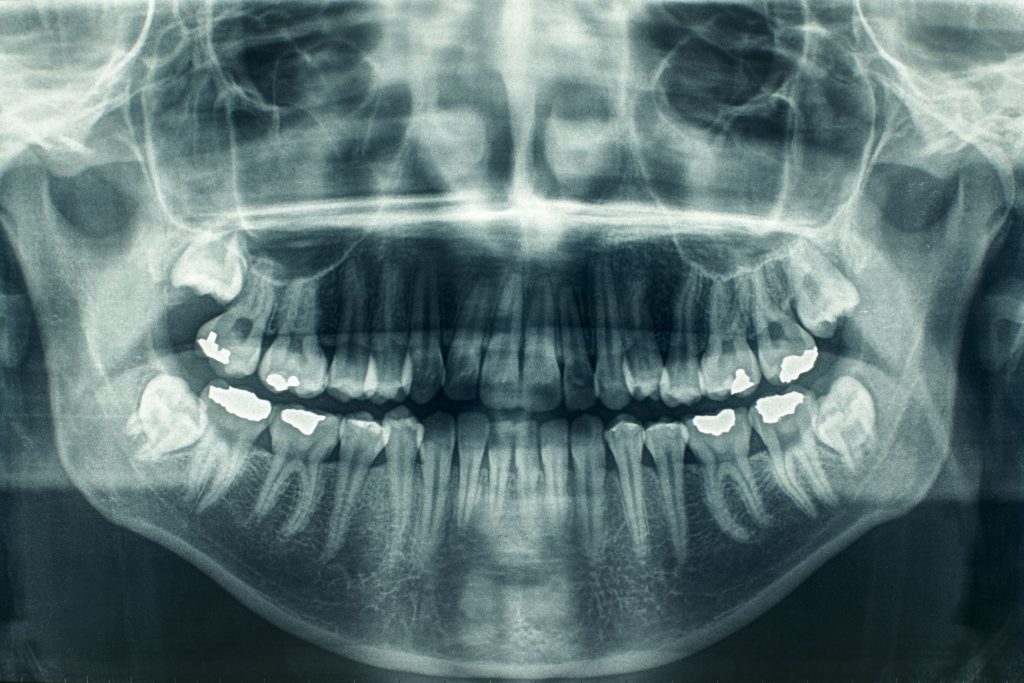

רשלנות כתוצאה מאי מומחיותו של רופא השיניים

פעמים רבות קורים מקרי רשלנות רפואית בתחום השיניים, כאשר הנזקים יכולים להתחיל מפגיעה בשן זו או אחרת, ועובר לפגיעות עצביות שונות, פגיעות היקפיות בשיניים ובעצמות הפנים, ובמקרים חריגים – לנזקים עצביים קשים.